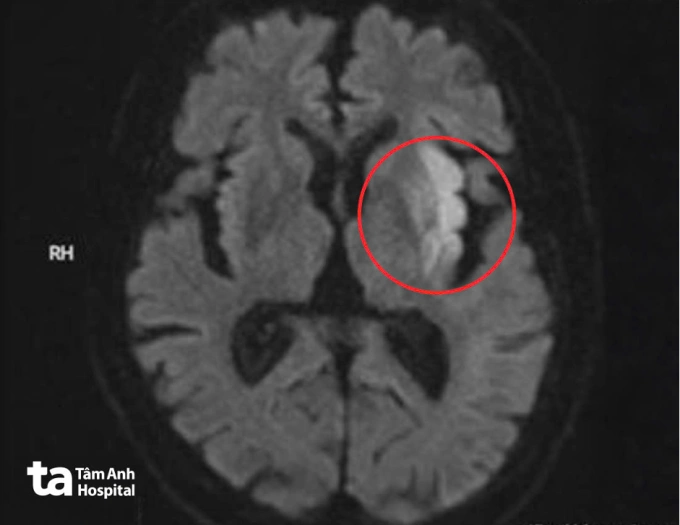

Bệnh viện kích hoạt quy trình “Code Stroke” tạo lối riêng cấp cứu đột quỵ. Kết quả chụp MRI 3 Tesla não của ông Trung cho thấy ổ nhồi máu cấp tại vùng nhân bèo, thùy trán và thùy đảo trái, kèm hình ảnh mất tín hiệu đoạn M1 động mạch não giữa trái, xác định tắc nghẽn mạch hoàn toàn.